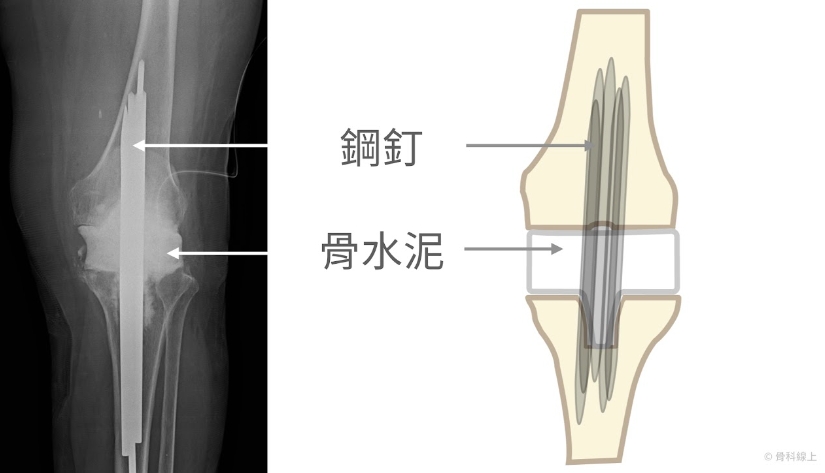

第一階段:拔除人工關節,置放含抗生素的骨水泥假體

X 光片上一樣可以出現表示鬆動的“黑線”

拔除人工關節,置放含抗生素的骨水泥假體術後 X 光片